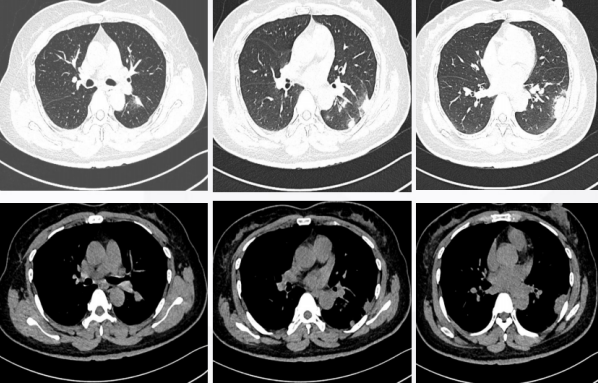

2021年7月16日行CT引导下肺穿刺活检。病理结果:(左下肺占位)穿刺:小块肺组织,肺泡间隔增宽,间质纤维组织增生,伴淋巴细胞、浆细胞浸润,肺泡腔内可见纤维素性渗出。特殊染色:抗酸染色(-),六胺银染色少数(+),PAS个别(+),PAS-D个别(+)。符合慢性炎,未排除特殊感染的可能,需结合临床实验室检查结果综合考虑。